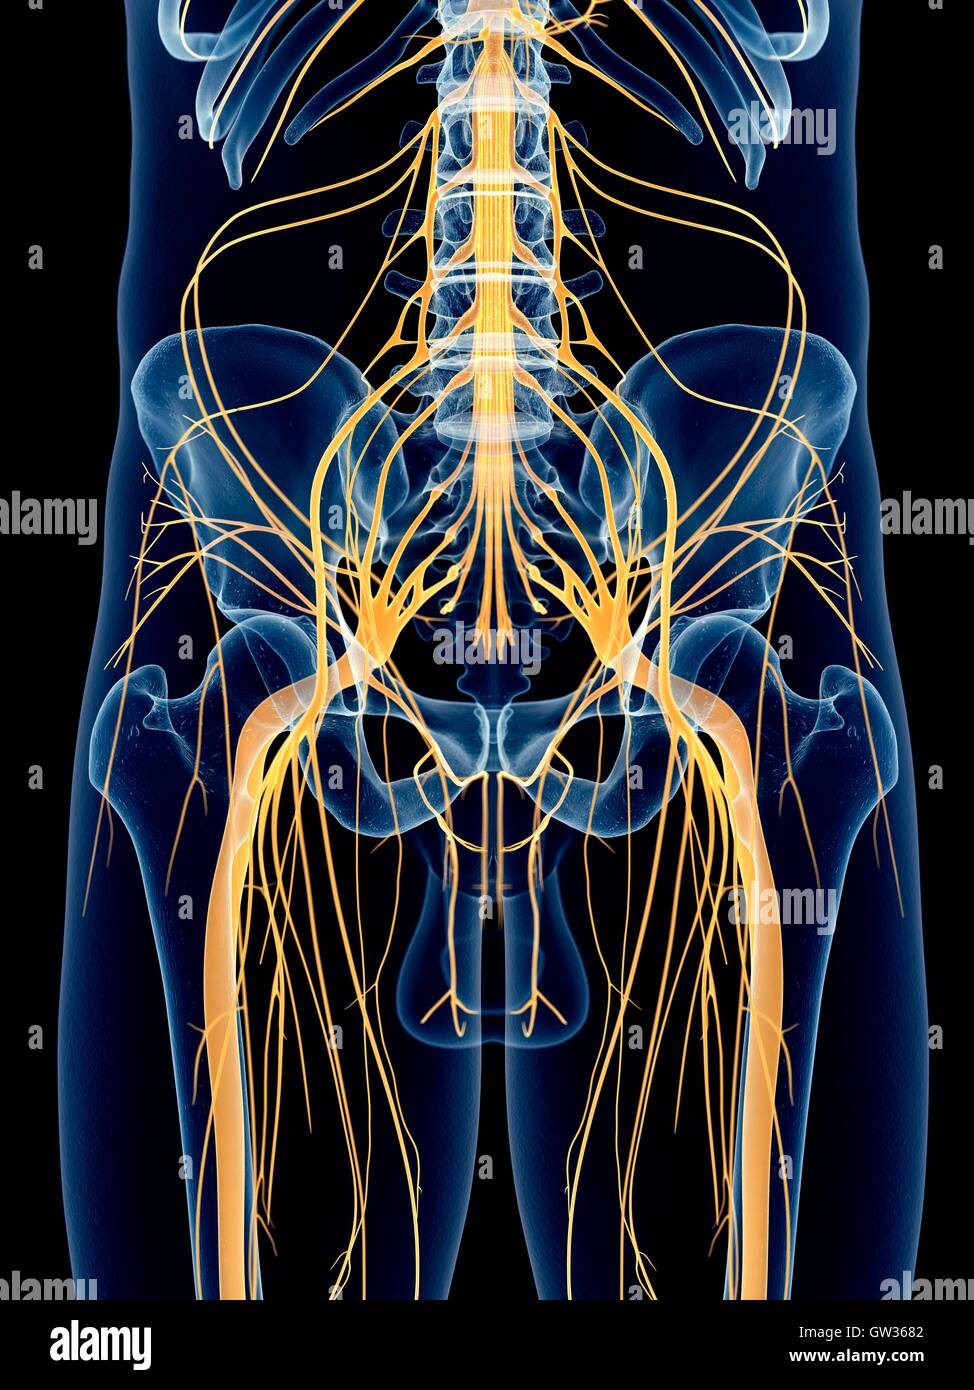

Nerf sciatique, l'illustration. Banque D'Imageshttps://www.alamyimages.fr/image-license-details/?v=1https://www.alamyimages.fr/photo-image-nerf-sciatique-l-illustration-118699394.html

Nerf sciatique, l'illustration. Banque D'Imageshttps://www.alamyimages.fr/image-license-details/?v=1https://www.alamyimages.fr/photo-image-nerf-sciatique-l-illustration-118699394.htmlRFGW3682–Nerf sciatique, l'illustration.